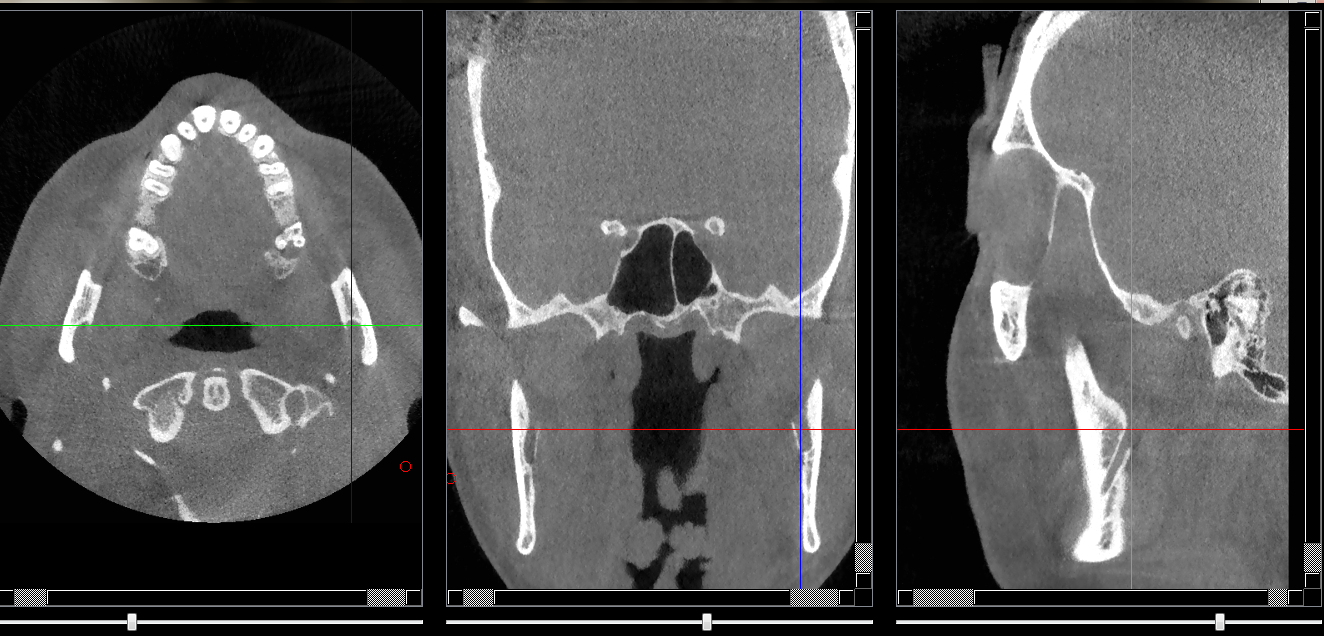

Structures osseuses

Canal alvéolaire inférieure (entrée du nai)

Repères anatomiques

Coupe transversale

• Début      : Il rentre par la face interne du ramus vers épine de spix en cheminant à l'intérieur de la branche horizontale pour sortir du foramen mentonier

Coupe frontale

Coupe saggitale